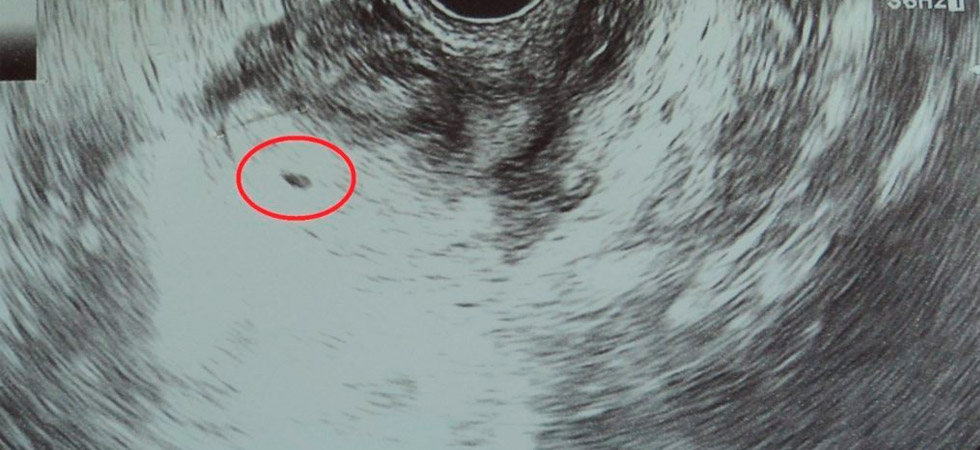

Вторая неделя беременности – это время когда эмбрион начинает пользоваться всеми правами, которыми можно пользоваться будущему малышу. В это время организм матери начинает свою заботу о нем, и он будет стараться сохранить зародыш и создавать ему самые оптимальные условия для развития.

С этого времени эмбрион питается не запасами яйцеклетки, а теми веществами, что может предоставить ему матка. Развитие его начинается с появлением зачатка трубки первичной кишки, которая необходима для того, чтобы эмбрион мог питаться и переваривать пищу. Во время второй недели беременности первичная кишка начинает удлиняться и делится на две части. В это время закладываются такие важнейшие органы будущего малыша как крупные сосуды и сердце.

Вокруг клетки образуется околоплодный пузырь, который заполняется околоплодными водами. В это же время образуется плацента, которая пуповиной соединяется с эмбрионом. Именно через неё малыш получает все необходимое ему питание.